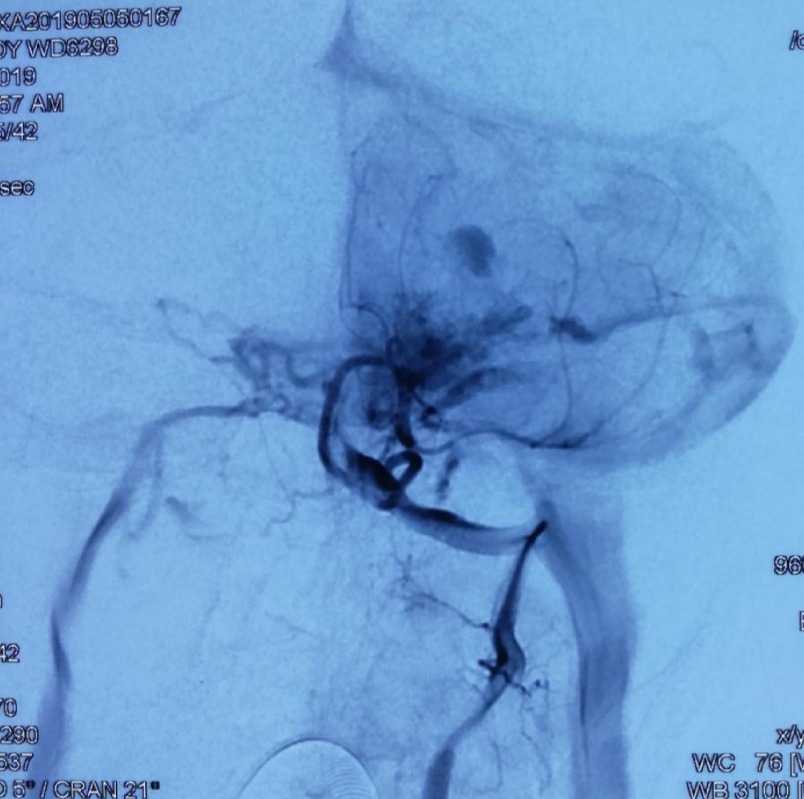

第⼀次DSA显⽰PICA供⾎

引流⾄⼄状窦

小脑后下动脉、小脑前下动脉参与供⾎

颈外动脉造影显⽰枕动脉参与供⾎